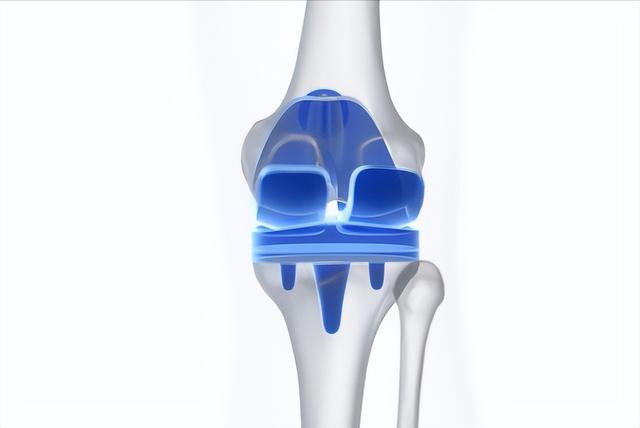

中医常说:“风寒湿邪,百病之源。”这“邪”一旦侵入筋骨,就像铁锈上了铰链,越动越紧,越紧越疼。关节这玩意儿,说白了就像门轴,平时不擦油不保养,时间一长,不但转不动,还会“咔哒咔哒”作响。

关节问题看似是“骨头”的事,实则是“全身气血”的事。中医讲究“肝主筋、肾主骨”,如果肝血不足、肾气亏虚,筋骨自然就“无粮可用”。再加上风寒湿邪趁虚而入,筋骨就像泡在冷水里的麻绳,硬、脆、易断。

你以为关节只是用来走路的?不,它承担的是你每天的生活节奏。一个人一旦行动受限,生活质量也会悄悄“打折”。

很多人把“关节僵硬”当成没事的小毛病,拖到最后才发现,不仅影响走路,还会引发腰椎间盘突出、骨质增生、滑膜炎等一系列连锁反应。那时就不是吃点药能解决的事了。